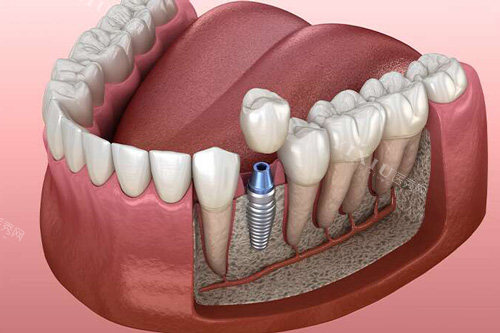

门牙种植牙是一种靠前的牙齿修复方式,它通过手术将人工牙根植入颌骨中,待人工牙根与颌骨紧密结合后,再安装牙冠,从而修复牙齿的形态和功能。种植牙具有较高的稳定性和耐用性,外观和功能都与自然牙齿十分接近,能有效改善患者的咀嚼功能和口腔美观度。

种植牙手术后,人工牙根需要与颌骨进行骨整合,这个过程通常需要 3 - 6 个月。在骨整合期间,种植体与周围骨组织的结合还不够牢固,过度咬硬物可能会导致种植体松动、移位,影响骨整合的结果,甚至导致种植失败。因此,在这段时间内,应严格避免用门牙种植牙咬硬东西。